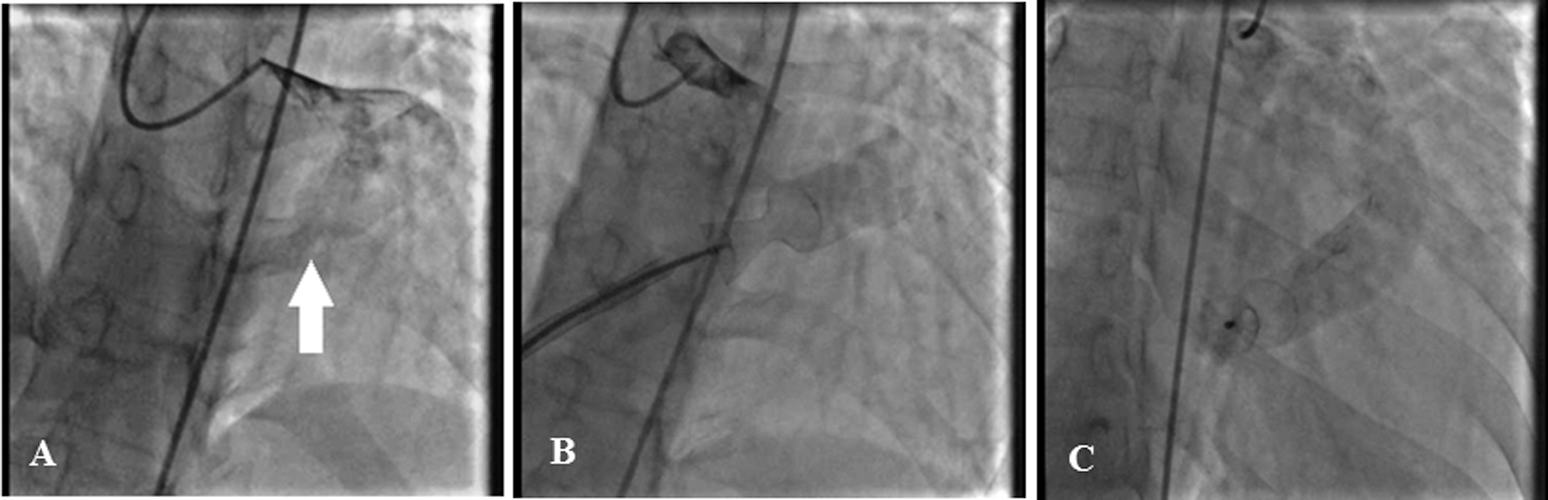

The coronary angiography revealed a large CAF from the LCx to the RA. Moreover, both left main and LCx were significantly dilated with no evidence of atherosclerotic coronary artery disease. Via the venous access through the femoral vein, a 14/18 Occlutech patent ductus arteriosus (PDA) occluder device (Occlutech international AB, Sweden) was deployed at the distal part of the fistula, resulting in a complete CAF closure with no residual shunt (Fig. 1). At 1 month’s follow-up, the patient was asymptomatic, and TTE and CTA confirmed the complete closure of the CAF with no residual shunt.

Figure 1: The coronary angiogram reveals a large coronary artery fistula, from the left circumflex artery to the right atrium (white arrow). Both left main and left circumflex coronary arteries are significantly dilated (Fig. A). Via the venous access through the femoral vein, a 14/18 Occlutech patent ductus arteriosus occluder device (Occlutech international AB, Sweden) was deployed successfully with no residual shunt (Figs. B and C)